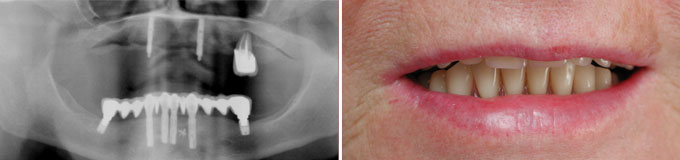

Il me manque de nombreuses dents, les autres sont perdues, je veux l’idéal.

Solution : on peut remplacer toutes vos racines manquantes ou perdues par autant de racines artificielles et vous redonner des dents fixes partout.

Toutes dents sont hélas perdues. Toutes les dents absentes sont remplacées par des couronnes sur implants.

J’ai des caries partout, des dents manquantes, je veux l’idéal.

Toutes les dents manquantes sont remplacées et le sourire refait.